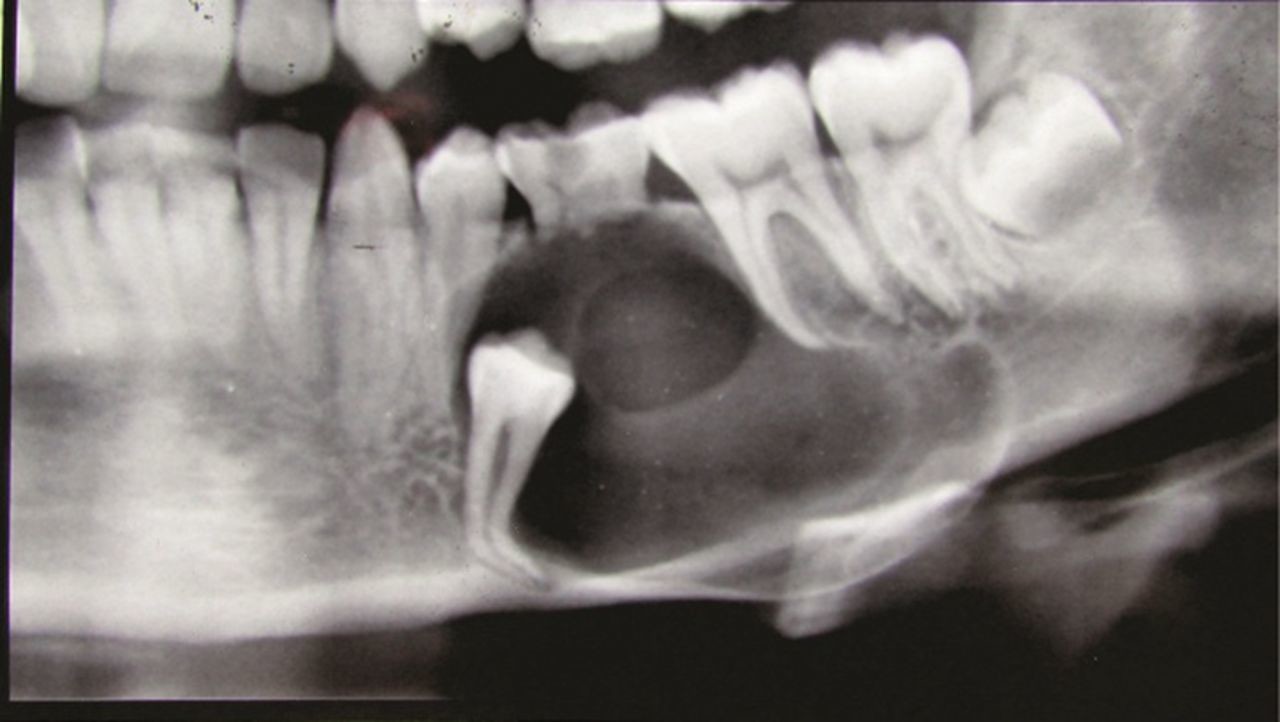

What is a dentigerous cyst?

Dentigerous cysts are the second most common type of odontogenic cyst, which is a fluid-filled sac that develops in the jaw bone and soft tissue. They form over the top of an unerupted tooth, or partially erupted tooth, usually one of your molars or canines. While dentigerous cysts are benign, they can lead to complications, such as infection, if left untreated.

How is it diagnosed?

Small dentigerous cysts often go unnoticed until you have a dental X-ray. If your dentist notices an unusual spot on your dental X-ray, they may use a CT scan or MRI scan to make sure it’s not another type of cyst, such as a periapical cyst or an aneurysmal bone cyst.

In some cases, including when the cyst is larger, your dentist may be able to diagnose a dentigerous cyst just by looking at it.

What are the complications?

Even if your dentigerous cyst is small and not causing any symptoms, it’s important to have it removed to avoid complications. An untreated dentigerous cyst can eventually cause:

infection

tooth loss

jaw fracture

ameloblastoma, a type of benign jaw tumor.